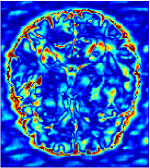

In this section, we test the generalizability of the proposed model that tests on unseen tasks. We fix the well-trained task-invariant parameter and only train for sampling ratios 15%, 25% and 35% with radio masks and sampling ratios 10%, 20%, 30% and 40% with Cartesian masks. In this experiment, we only used 100 training data for each CS ratio and apply a total of 50 epochs. The averaged evaluation values and standard deviations are listed in Table 5.4 and 5.4 for reconstructed T1 and T2 brain images respectively that proceed with radio masks, and Table 5.4 shows the qualitative performance for reconstructed T2 brain image that applied random Cartesian sampling masks. In T1 image reconstruction results, meta-learning improved 1.6921 dB in PSNR for 15% CS ratio, 1.6608 dB for 25% CS ratio, and 0.5764 dB for 35% comparing to the conventional method, which in the tendency that the level of reconstruction quality for lower CS ratios improved more than higher CS ratios. A similar trend happens in T2 reconstruction results with different sampling masks. The qualitative comparisons are illustrated in Figure 2, 4 and 5 for T1 and T2 images tested in skewed CS ratios in radio masks, and T2 images tested in Cartesian masks with regular CS ratios respectively. In the experiments that conducted with radio masks, meta-learning is superior to conventional learning especially at CS ratio 15%, one can observe that the detailed region in red boxes keeps edges and is more close to the true image, while conventional method reconstructions are hazier and lost details in some complicated tissue. The point-wise error map also indicates that Meta-learning has the ability to suppress noises.

In general supervised learning, training data need to be in the same or similar distribution, heterogeneous data exhibits different structure variations of features which hinders CNNs to extract features efficiently. In our experiments, raw measurements sampled from different ratios of compressed sensing display different levels of incompleteness, these undersampled measurements do not fall in the same distribution but they are related. Different sampling masks are shown at the bottom of Figure 1 and 2 may have complemented sampled points, in the sense that some of the points which sampling ratio mask does not sample have been captured by other masks. In our experiment, different sampling masks provide their own information from their sampled points so that four reconstruction tasks help each other to achieve an efficient performance. Therefore, it explains the reason that Meta-learning is still superior to conventional learning when the sampling ratio is large.